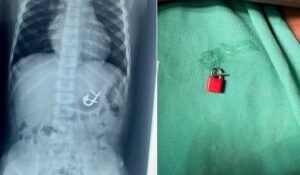

Criança engole cadeado com as chaves e passa por endoscopia para remoção